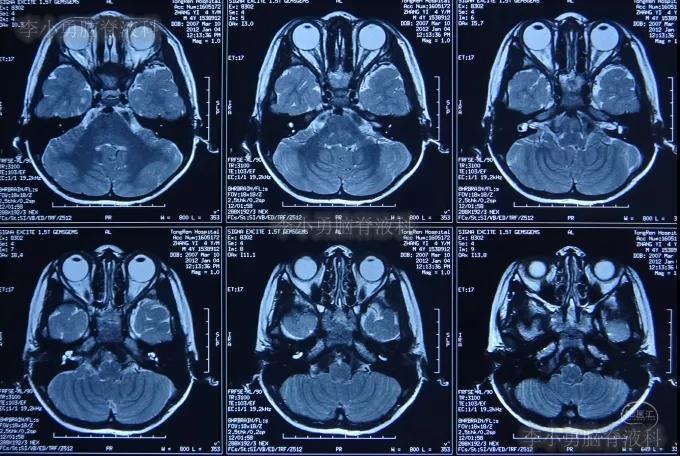

患儿先天性聋哑,在3岁时即在2010年8月17日,于第1家北京某著名三甲医院进行了颅底耳蜗周结构的CT检查(图-1)。

图-1:2010年8月17日耳蜗周颅底CT

在5岁时2012年,为了进行人工耳蜗植入术,再次住入第1家的北京某著名三甲医院;在住院后的2012年1月4日,进行了术前必须的脑和颅底的核磁检查(图-2)。

图-2:2012年1月4日颅底和脑的核磁检查